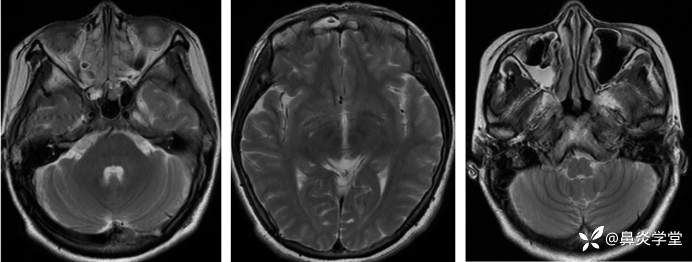

嗅通路 MRI:双侧嗅球、嗅束形态及信号未见明显改变,嗅三角区未见明显肿块。双侧梨形区、边缘。下丘脑未见明显形态及信号改变。附见:全组副鼻窦炎。

此外,该患者的症状以嗅觉减退为主,嗅通路 MRI 检查未见明显异常,排除嗅通路结构及嗅中枢功能异常,可进一步明确为鼻-鼻窦炎相关的嗅觉障碍[3]。